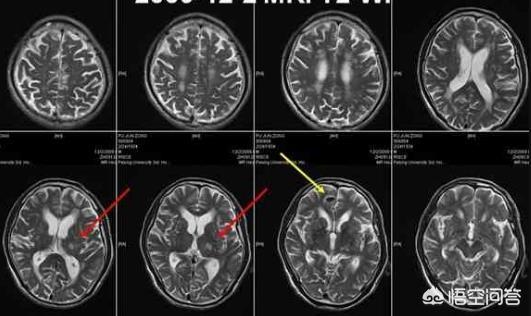

脳梗塞発症後24〜48時間後に脳のCT検査を行うと、対応する部位に境界のはっきりしない低密度の病巣が認められ、何らかの占拠作用がある可能性がある。脳磁気共鳴(MRI)検査では、病変部のT1低信号と加重画像のT2高信号によって示される脳梗塞を早期に発見することができ、MRIはより小さな梗塞病変を検出することができる。

海綿状脳梗塞は、一般的な脳血管障害の一つであり、持続性高血圧と小動脈硬化に起因する特殊な脳血管障害で、直径100〜400μmの深部貫通枝の閉塞による微小梗塞である。末期には、軟化した微小病巣から壊死組織が除去され、小さな嚢胞状の空洞が残るため、海綿状脳梗塞と呼ばれる。

病理診断名にちなんで命名され、脳の新鮮または古い深在性小梗塞の総称である。好発部位は大脳基底核と大脳皮質基底部であり、発生頻度は側坐核、尾状核、視床、大脳皮質、内被殻、白質であり、大脳皮質と小脳皮質は発生しない。

海綿状脳梗塞は、長期高血圧、高脂血症、糖尿病などの危険因子の役割で、脳組織の小さな貫通動脈を指し、血管壁の病変、最終的には内腔の閉塞、その結果、遠位脳組織の虚血と無酸素性壊死、貪食による壊死脳細胞、除去、小さな空洞の形成、したがって、我々は海綿状脳梗塞と呼ぶ、梗塞の大きさの梗塞巣は、一般的に1.5〜2センチメートル以下です。2cm以下である。